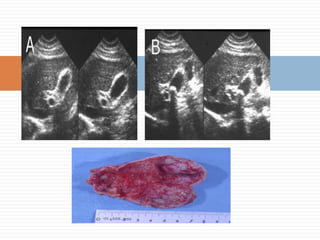

Colecistitis Aguda AlitiásicaA y B- En este caso en la eco se ven sólo 2 de los 5 signos clásicos (bilis ecogénica y engrosamiento de la pared vesicular.)

Colecistitis Aguda AlitiásicaAy B- En este caso en la eco se ven sólo 2 de los 5 signos clásicos (bilis ecogénica y engrosamiento de la pared vesicular.)

Colecistitis AgudaColecistitis Aguda Grave ComplicadaEsta patología se ve en pacientes graves (cardiópatas, grandes quemados, politraumatizados, pacientes en shock, etc.) y el factor patogénico es la hipo perfusión de la pared vesicular.B- Pieza operatoria que muestra una colecistitis alitiásica con gangrena vesicular por isquemia

Colecistitis AgudaColecistitis AgudaGrave ComplicadaEsta patología se ve en pacientes graves (cardiópatas, grandes quemados, politraumatizados, pacientes en shock, etc.) y el factor patogénico es la hipo perfusión de la pared vesicular.B- Pieza operatoria que muestra una colecistitis alitiásica con gangrena vesicular por isquemia